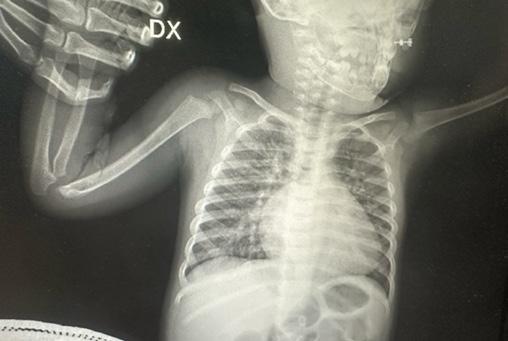

Un bambino di 15 mesi giungeva in PS per tosse, rifiuto dell’alimentazione e dispnea. In anamnesi: distress respiratorio neonatale, desaturazioni post-prandiali e wheezing ricorrente. All’esame obiettivo: polipnea, rientramenti sottocostali, tachicardia, SpO₂ 85% in aria ambiente, rantoli e sibili diffusi. La radiografia evidenziava accentuazione della trama broncovascolare e cardiomegalia [Figura 1]. L’emogas arterioso mostrava ipercapnia severa (pCO2 70 mmHg), ipossia (pO2 54,4 mmHg)

1. Radiografia del torace: “Iperespansione polmonare bilaterale. Diffusa accentuazione reticolo nodulare della trama vascolo-bronchiale bilaterale, con segni di confluenza parenchimale retrocardiaca basale sinistra e areola di ipodiafania paramediastinica destra. Mediastino in asse. Ombra cardiaca volumetricamente ai limiti alti”.

e bicarbonati notevolmente aumentati (43 mmol/L). Il tampone nasofaringeo risultava positivo per VRS. Per peggioramento clinico, si trasferiva in TIP, dove riceveva ventilazione invasiva per 7 giorni, successivamente NIV notturna e HFNC diurna. Per persistenza dell’ipercapnia, effettuava monitoraggio cardiorespiratorio notturno (saturimetria e capnometria).